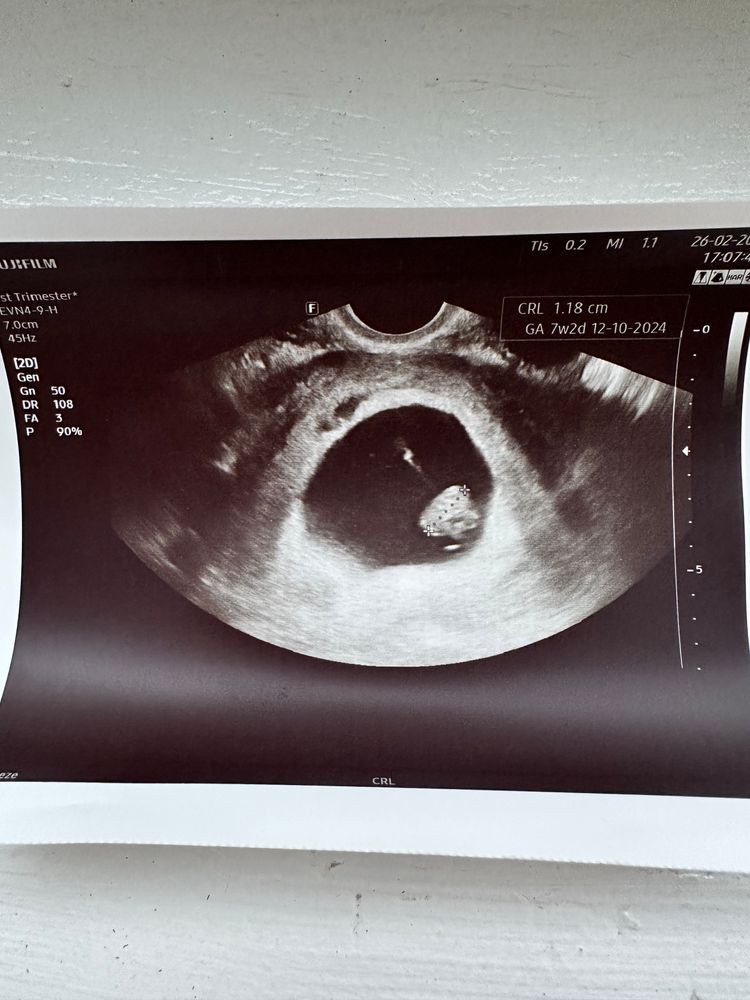

Zelenka, дело в том,что этот гинеколог мне даже выписку с узи не дал,ничего не сказал,сказал просто что всё хорошо и дал снимок с узи Изображение

Натик, я просто не понимаю там один сантиметр ктр или это один миллиметр

Катерина, у вас 1 см 17 мм по фото.

Натик, тогда точно должно быть слышно сердечко 😭

Милена, здравствуй,если я правильно поняла то 1.17 Изображение